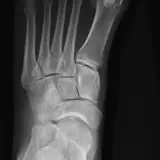

Over 2,100 interactive radiology cases, curated by radiologists for your level of training. Scroll, window, and view cases full screen — just like on PACS. Click linked findings in each writeup to jump straight to them on the image. Cases include sample reports, a focused discussion section, original illustrations, and videos.

PACSで期待されるツールを完備した完全インタラクティブな症例 — スクロール、ウィンドウ調整、ズーム、パン、計測、ROI、フルスクリーンモード。

重要な所見を症例画像上に直接ハイライトする豊富なアノテーション。症例解説内のリンクされた所見をクリックすると、スキャン上の正確な位置へジャンプできます。